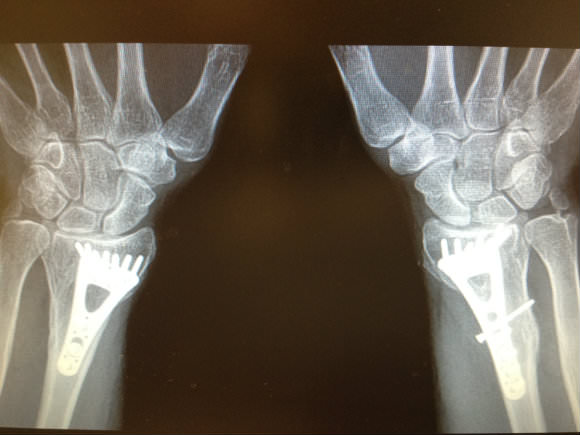

JL is a gifted toymaker by profession, nearly ending his career after a fall from a ladder shattered both wrists. Simultaneous volar plate fixation via open surgery to wrists was performed allowing him to go back to his trade. One was so complex that a revision surgery was needed some weeks later. However, JL went on to not only regain full use of his hands, as seen here, but he embarked on a fitness program and got in much better shape than he was in before. Despite titanium plates in both wrists, he can now do more pushups and bench press much more weight than before the surgery. This indicates that even with a complex injury, a motivated patient can get back to normal if the initial surgery is correctly done. The importance of a specialist cannot be underestimated.